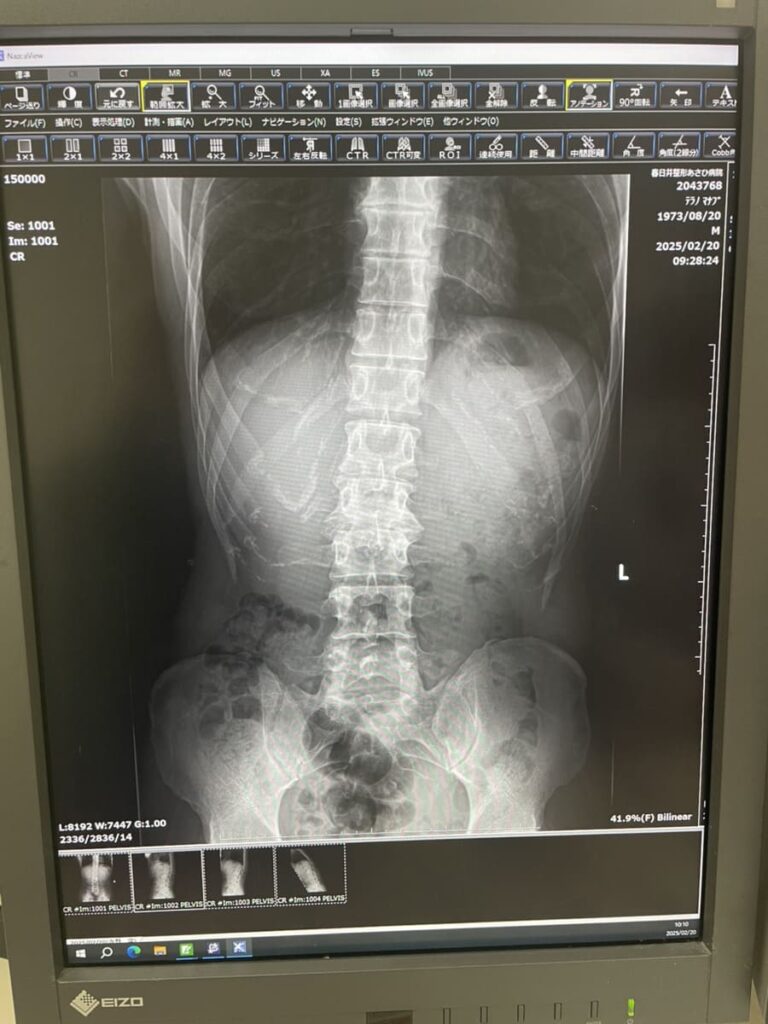

背骨が曲がっています。

↓画像を見てください,

レントゲン写真では、変形のある腰椎以外にも椎間が狭くなっている所がありますし、S字カーブが崩れているように見受けられます。

背骨が曲がっているのは今回のレントゲンで見ることが出来ましたが、曲がっているのは自覚していました。